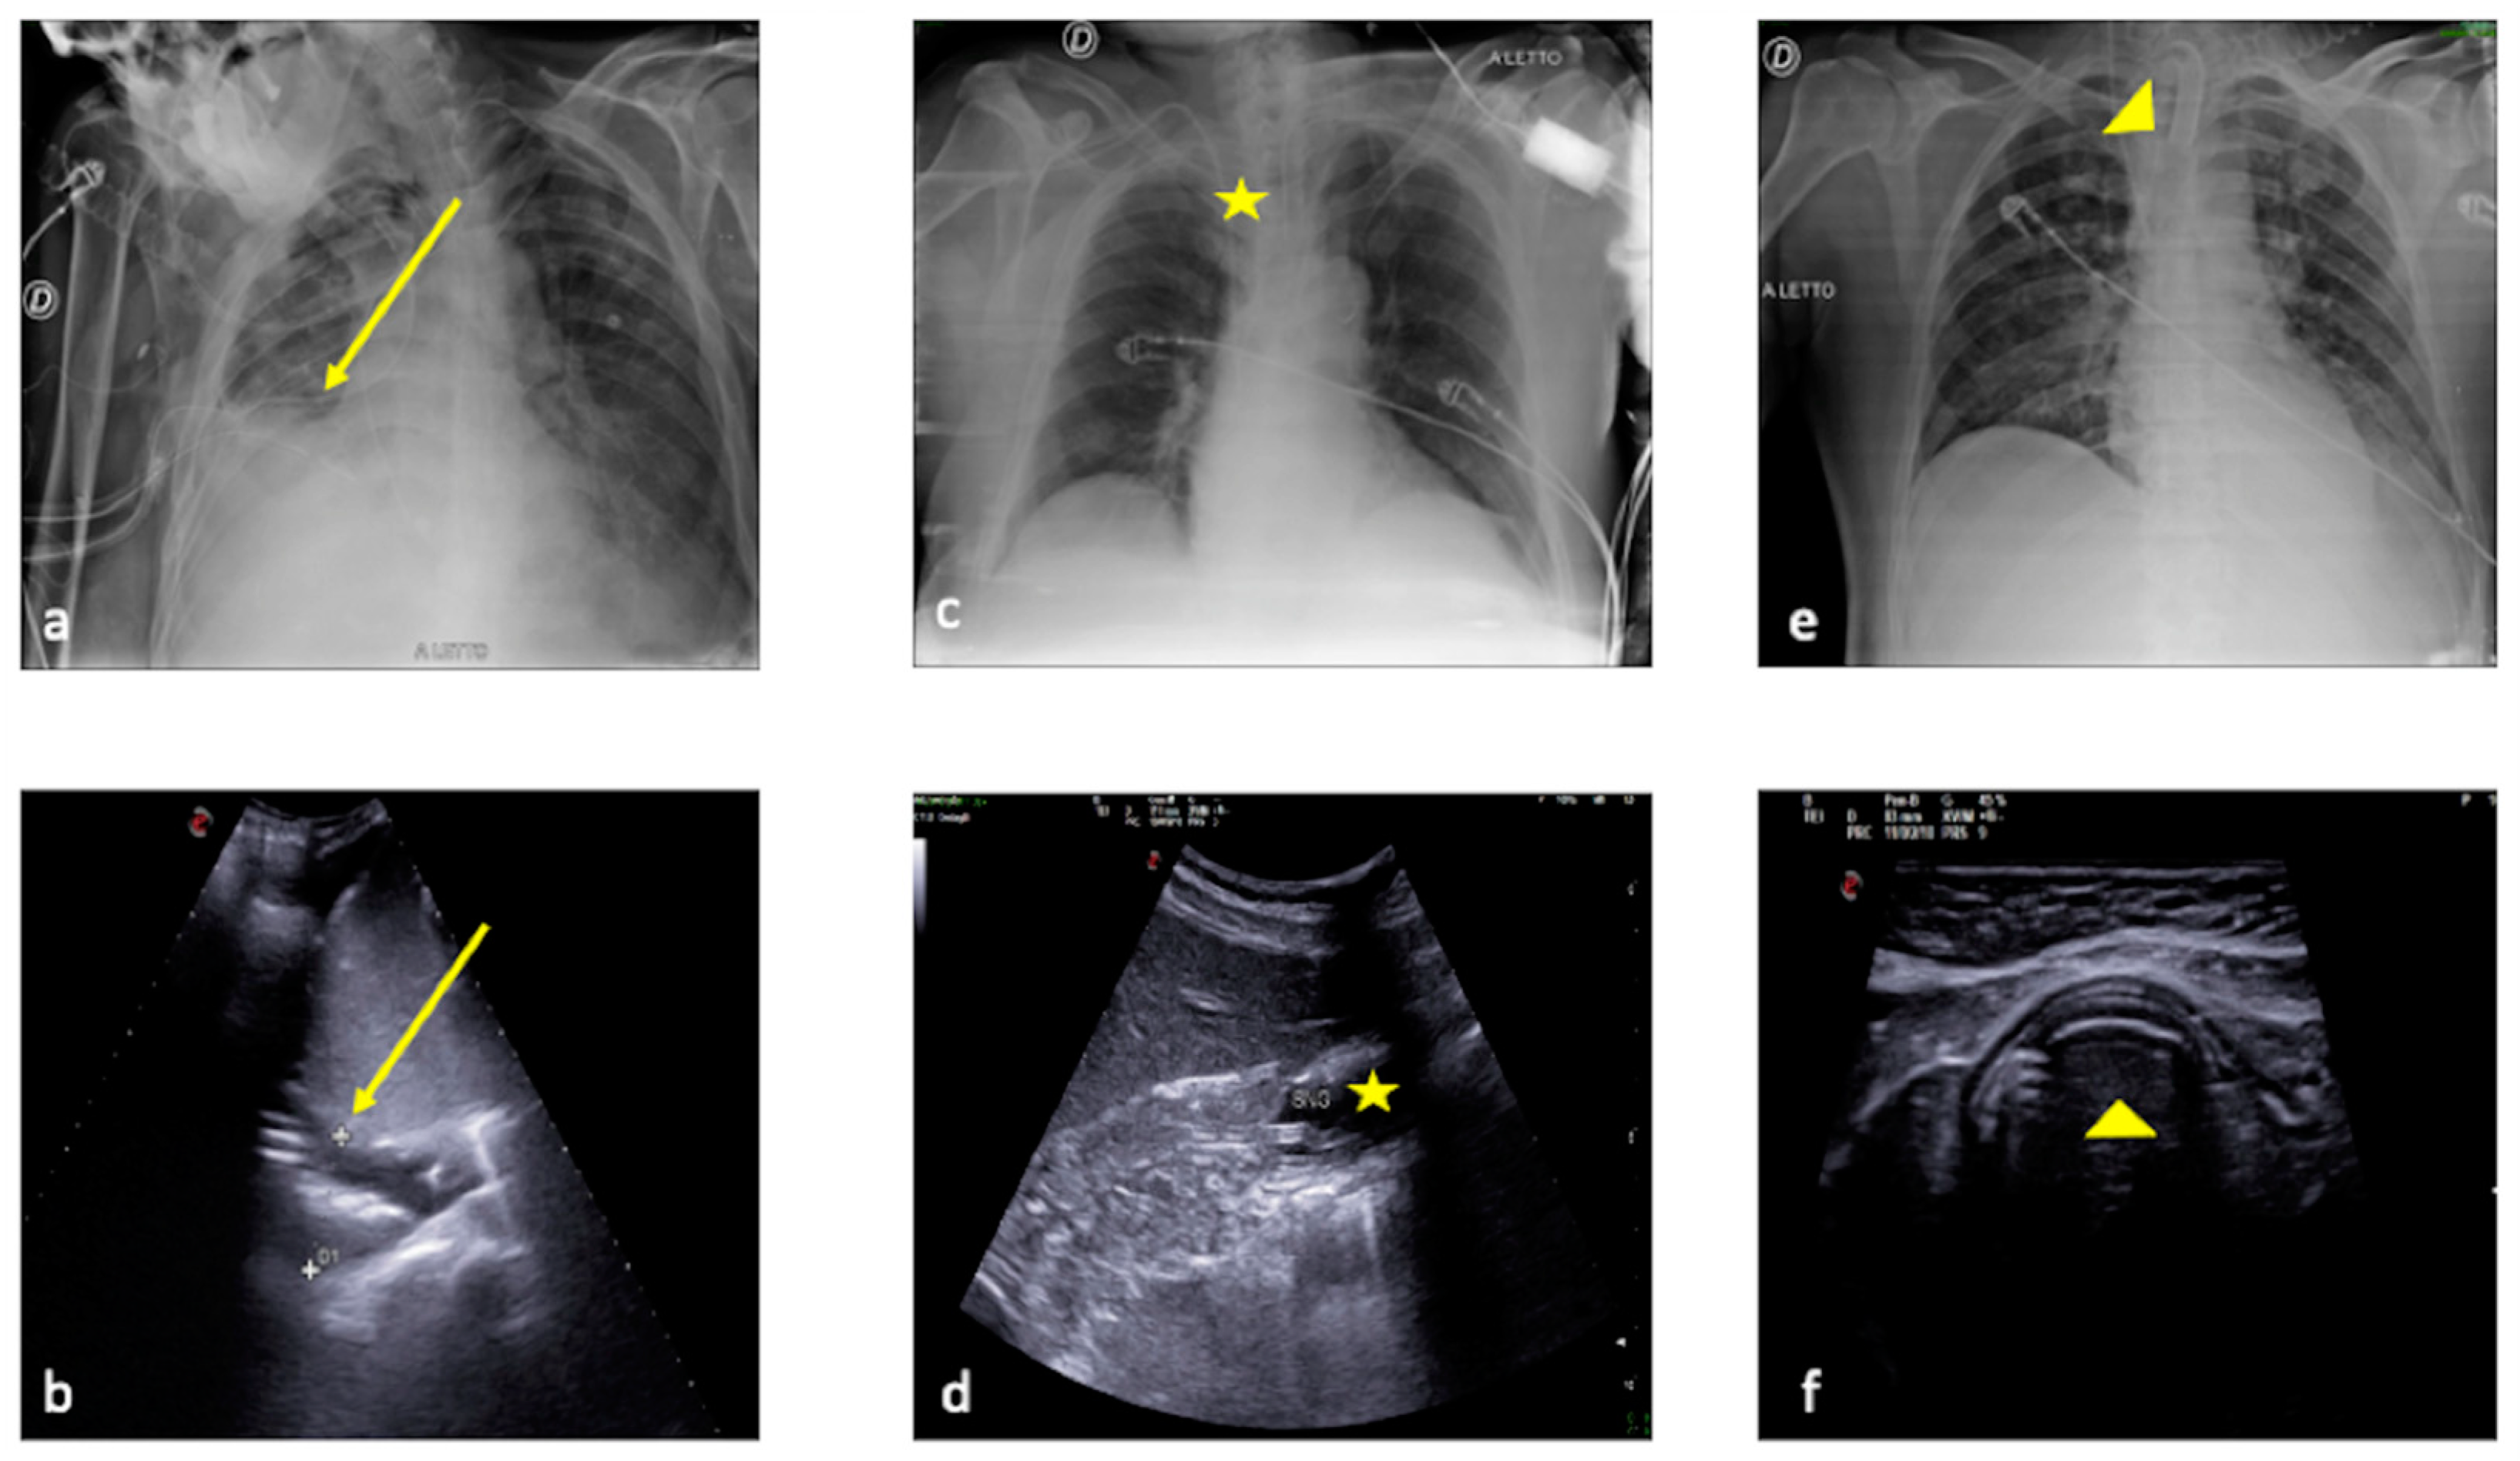

2.1. Atelectasis

2.2. Pneumonia

2.3. Pleural Effusion